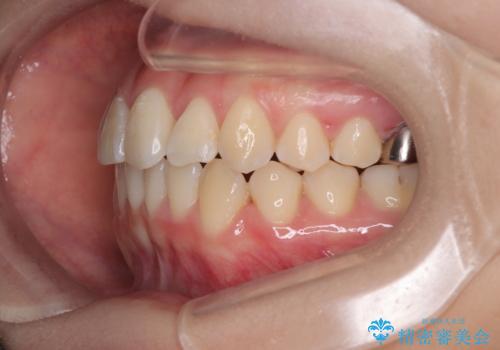

矯正治療期間はわずか10か月と、比較的短期間で終了しました。

前歯のデコボコがなくなり、見た目の印象が大きく変わっただけでなく、歯磨きがしやすくなり、むし歯や歯周病のリスクが大きく減少しました。